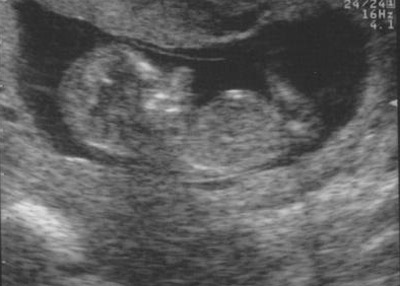

I went to the doctor today for a routine checkup on the baby. It was my first time to meet the doctor, and after asking my huge list of questions and getting answer after answer that impressed me, I must say I really like him a lot. My questions included everything from heart defects, to intervention during labor, to postpartum depression. I found out they are able to do the type of ultrasound to check for heart defects we need here in Springdale, but I still requested to go down to Little Rock, as I am comfortable with the doctors there. So that is in the works to be scheduled, my guess is it will be sometime in March. After talking with him for about 30 minutes he did a quick ultrasound to just peak at the baby and it is amazing how much they grow in just 4 weeks. I'll show you this morning's ultrasound next to the one from a month ago and you can see how much has changed.